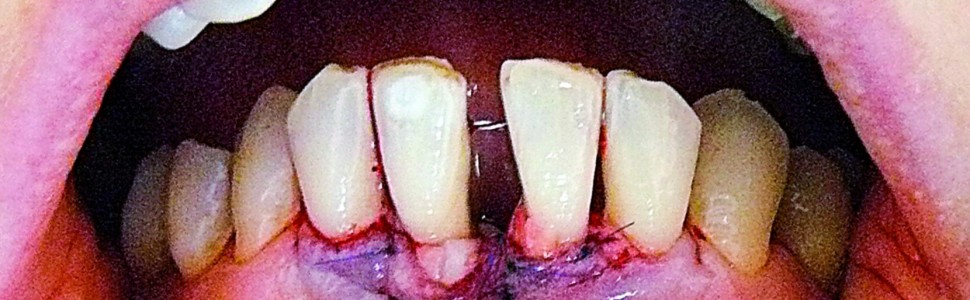

Ryc. 1. Stan przed rozpoczęciem leczenia – recesje RT3 w okolicy dolnych zębów siecznych centralnych oraz deficyt brodawki centralnej.

Z wywiadu ustalono, że pacjentka nieregularnie korzystała z opieki stomatologicznej, głównie było to leczenie próchnicy i profesjonalne oczyszczanie zębów. Jej stan zdrowia był ogólnie dobry, nie przyjmowała żadnych leków, a głównym problemem stała się zaburzona estetyka. W czasie badania klinicznego nie stwierdzono obecności stanu zapalnego, nie obserwowano krwawienia, głębokość kieszonek przyzębnych nie przekraczała 4 mm. Obserwowano niewielką ilość miękkich i twardych złogów nazębnych. Manifestacją zaawansowanej redukcji tkanek przyzębia były liczne recesje, ruchomość przyśrodkowych zębów siecznych górnych i dolnych na granicy I i II stopnia oraz migracja patologiczna skutkująca dysfunkcją żucia. Największe recesje obserwowano na powierzchni wargowej i mezjalnej przyśrodkowych zębów siecznych dolnych. W okolicy zęba 41 odpowiednio 3,5 i 6 mm, w okolicy zęba 31 odpowiednio 2 i 3,5 mm. Były to recesje typu 3 (RT3), dodatkowo występował deficyt dolnej brodawki centralnej typu 2 według Nordlanda i Tarnowa, ekstruzja zębów przednich z rotacją zęba 41 (ryc. 1) oraz diastema. Wykonane zdjęcie rentgenowskie ujawniło poziomą destrukcję części zębodołowej żuchwy w przestrzeni pomiędzy przyśrodkowymi zębami siecznymi dolnymi (ryc. 2). Pacjentka wymagała kompleksowej rehabilitacji, której głównym elementem było leczenie ortodontyczne i protetyczne. W pierwszej fazie zaplanowano jednak chirurgiczne pokrycie recesji, przygotowujące okolicę zębów siecznych dolnych do leczenia ortodontycznego. Celem była częściowa redukcja recesji dziąsłowych, poszerzenie strefy dziąsła skeratynizowanego w obszarze przyśrodkowych zębów siecznych dolnych, a także uzysk przyczepu łącznotkankowego w przestrzeni międzyzębowej z poprawą położenia brodawki międzyzębowej. Dwa tygodnie przed planowanym zabiegiem wykonano skaling z gładzeniem powierzchni korzeni, instruktaż higieny oraz tymczasowo – na czas leczenia chirurgicznego unieruchomiono zęby sieczne dolne, wykorzystując splecioną ligaturę drucianą zamocowaną materiałem kompozycyjnym na powierzchni językowej zębów.